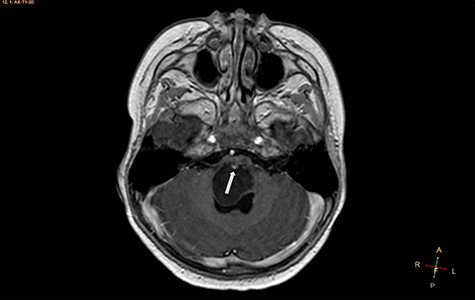

Axial T2-weighted image, showing a hyperintense, cystic mass inside the medulla oblongata. Exceptionally, the lesion appears to progress from extra-axial to intraparenchymal (arrow).

Two widely accepted hypotheses have been suggested to explain the establishment of extra-axial and intra-axial ECs. Theoretically, ECs form due to aberrations in ectodermal residues or the sequestration of ectodermal components during an early stage of gestational growth, between the 3rd and 5th weeks. The remnants of these ectodermal cells eventually proliferate, forming an EC [3, 4]. Retrospectively, the findings shown in Fig. 2 appear to show the progression of the lesions from the extra-axial to the intraparenchymal medulla oblongata; therefore, we have contributed additional evidence to reinforce the hypothesis regarding the primitively extra-axial root of EC development.